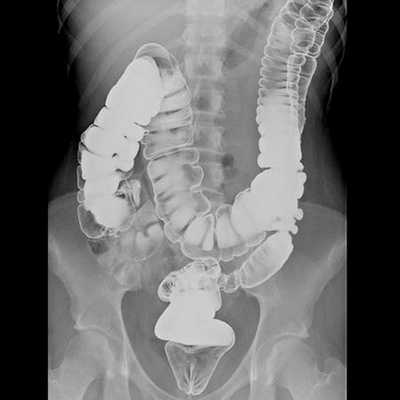

Методы диагностики

При подозрении на рак кишечника в первую очередь назначают колоноскопию. Во время процедуры в толстый кишечник вводят через задний проход специальный инструмент в виде тонкой длинной гибкой трубки — колоноскоп. На конце колоноскопа находится миниатюрная видеокамера и источник света. Увеличенное изображение транслируется на экран аппарата, таким образом, врач имеет возможность осмотреть слизистую оболочку кишки изнутри.

После того как во время колоноскопии обнаружена злокачественная опухоль, зачастую необходимо уточнить некоторые подробности. Врачу нужно выяснить, насколько сильно новообразование проросло за пределы кишки, распространилось ли оно в регионарные лимфоузлы, есть ли отдаленные метастазы. Для этого используют дополнительные методы диагностики: КТ, МРТ, ПЭТ, рентгенографию костей и грудной клетки, УЗИ органов брюшной полости.